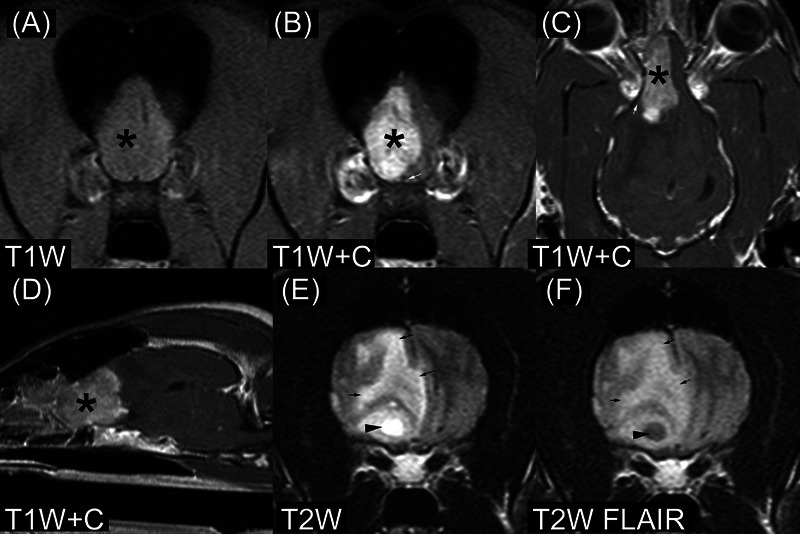

关于犬颅内或脊髓上皮瘤的核磁共振成像外观,公开发表的描述很少。在这项多中心、回顾性、二次分析、病例系列研究中,三位兽医放射科专家独立审查并记录了六只经组织病理学确诊的狗肾上皮瘤(三例颅内病例和三例脊髓病例)的核磁共振成像检查特征。如果对具体特征存在分歧,则达成共识。所有颅内外胚窦瘤都位于前脑,在 T1 加权(T1W)和 T2 加权(T2W)图像中信号强度不均匀,对比度增强不均匀,T2W 图像中信号强度过高。两例脑外膜瘤位于脑室内,一例位于轴内。其他成像特征包括内部囊肿样结构、内部出血和周围水肿。患脊髓外胚瘤的狗的髓内病变位于颈部或胸部脊髓。脊髓外皮瘤在 T1W 图像中呈等密度和均匀性,在 T2W 图像中呈高密度。病变相对于脊髓中央管的位置各不相同。所有三个脊髓外胚瘤体周围都有 T2W 高密度和中度异质对比度增强。没有一个脊髓外胚瘤内生囊肿样结构。其中一个脊髓外胚瘤体有下坠转移(弥漫性、脑外膜)的迹象。犬肾上皮瘤的磁共振成像特征与其他脑部和脊髓疾病的特征重叠。对于患有脑室内、前脑轴内或脊髓髓内肿块的犬,应将附脑瘤作为鉴别诊断的一个因素。

There are few published descriptions of the MRI appearance of canine intracranial or spinal cord ependymoma. In this multicenter, retrospective, secondary analysis, case series study, three veterinary radiologists independently reviewed and recorded imaging characteristics of MRI studies in six dogs with histopathologically confirmed ependymoma (three intracranial and three spinal cord cases). A consensus was reached when there was disagreement on specific features. All intracranial ependymomas had forebrain location, heterogeneous signal intensity in T1-weighted (T1W) and T2-weighted (T2W) images, heterogeneous contrast enhancement, and hyperintensity in T2W images. Two ependymomas had an intraventricular location; one was intra-axial. Other imaging features included intralesional cyst-like structures, intralesional hemorrhage, and perilesional edema. Dogs with spinal cord ependymoma had intramedullary lesions located in the cervical or thoracic spinal cord. Spinal cord ependymomas were isointense and homogeneous in T1W images and hyperintense in T2W images. Lesion location relative to the central canal of the spinal cord was variable. All three spinal cord ependymomas had perilesional T2W hyperintensity and moderate, heterogeneous contrast enhancement. None of the spinal cord ependymomas had intralesional cyst-like structures. One spinal cord ependymoma had evidence of drop metastases (diffuse, leptomeningeal). MRI features of canine ependymomas overlap with those of other diseases of the brain and spinal cord. Ependymoma should be considered a differential diagnosis for dogs with intraventricular, intra-axial forebrain, or intramedullary spinal cord masses.